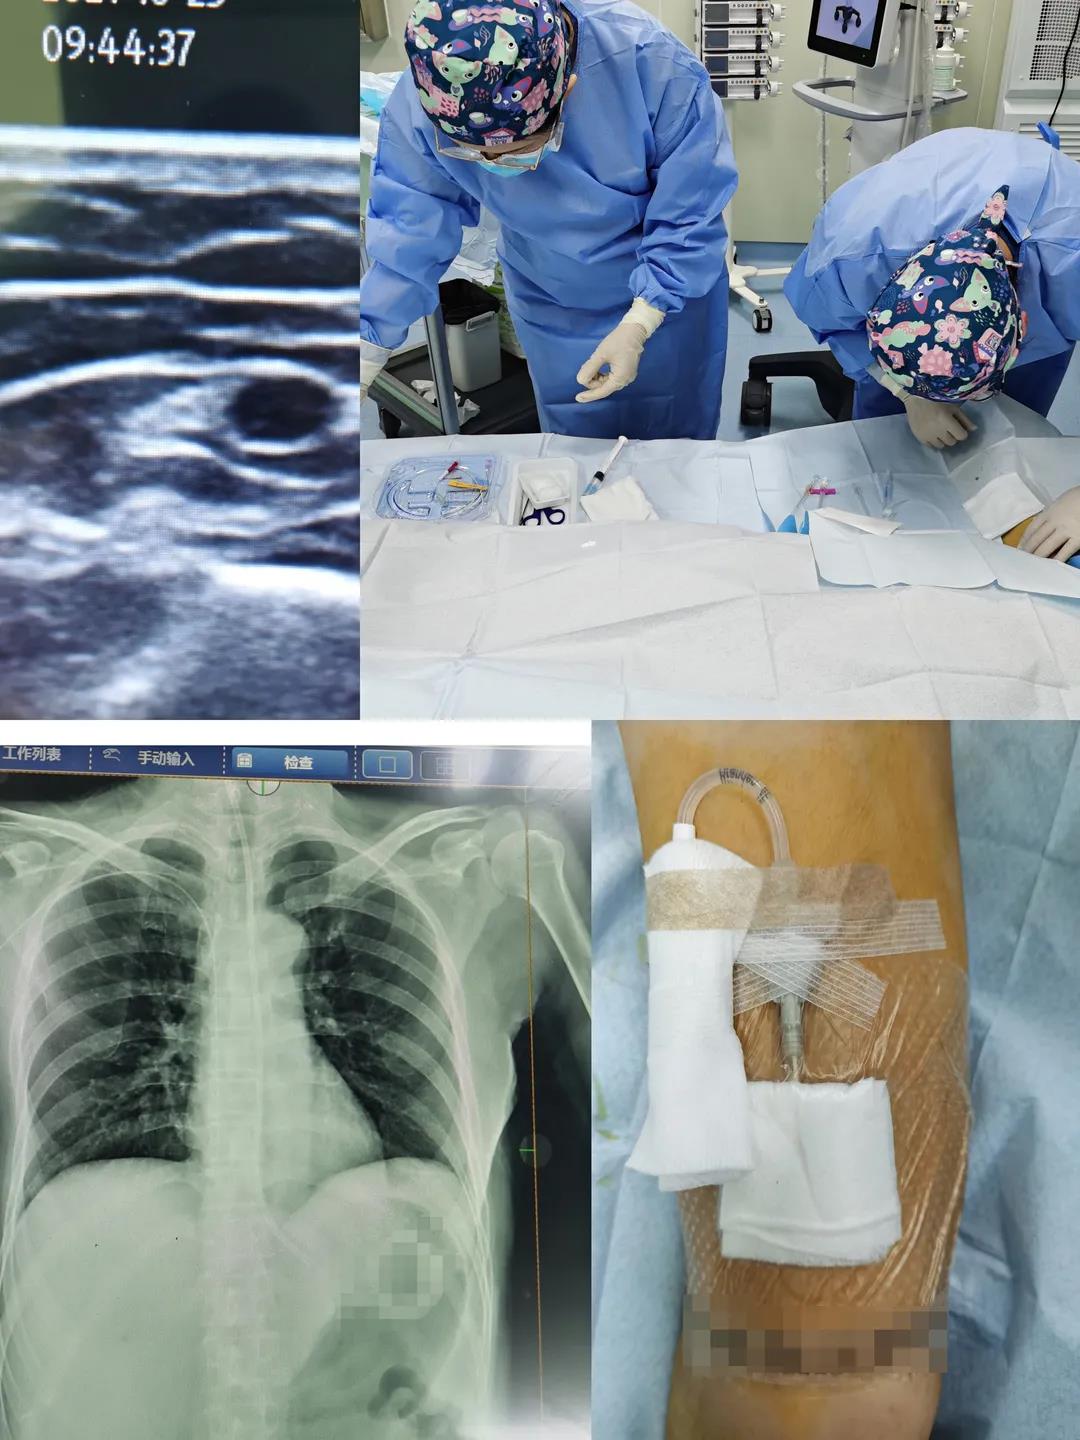

近日,新生儿科开展我院首例新生儿胸腔穿刺成功救治危重患儿,家属送锦旗深表感谢!

重症医学科护士长王婷婷在B超引导下为普外科患者行右侧贵要静脉PICC置管术,为急危重症患者提供安全可靠的静脉通路,减少了不必要的穿刺,极大降低了导管相关血流感染的风险,为患者提供高效优质的护理服务,我们一直在行动……